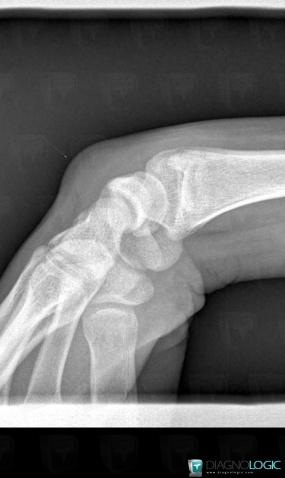

Synovial cyst, Other soft tissues/nerves - Hand, X rays

Here is the specific information in the key image above:

- Diagnosis Synovial cyst, Location(s) Other soft tissues/nerves - Hand, with gamuts Soft tissue mass about a joint